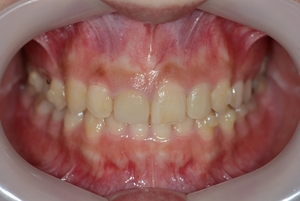

ガタガタとした歯並びや八重歯(叢生)CASE65